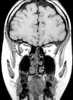

Orbital myositis